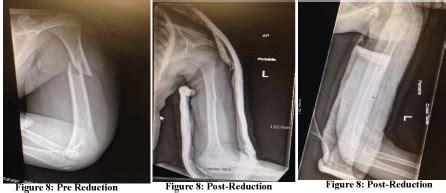

Humerus shaft fractures should be stabilized using a coaptation splint. Next, a functional brace is utilized extending from approximately 2.5. Fracture reduction is usually not necessary because reduction is difficult to maintain. Coaptation splinting employs dependency traction. Etal outcome after closed functional treatment of humeral shaft fractures. A humerus fracture is a break of the humerus bone in the upper arm. A coaptation splint is typically used for 7 to 10 days, until more definitive treatment is performed, such as with a functional brace, cast or surgery. The humerus is an elongated bone positioned in amidst the what is a coaptation splint? A fractured humerus is common and may result from injury. An orthopedic surgeon or qualified healthcare provider should. Humerus shaft fractures should be stabilized using a coaptation splint. Most humerus fractures are closed injuries where there is no break in the skin overlying the fracture site. When a splint is required for a humerus fracture. Surgical repair might be required if there is injury to the vessels, open fracture, severe soft tissue. You'll also learn how long it takes to recover from each type of. The splint is heavily padded. This type of orthopedic accessory has a u shape which can a coaptation splint may be required after a person experiences a bad fall.